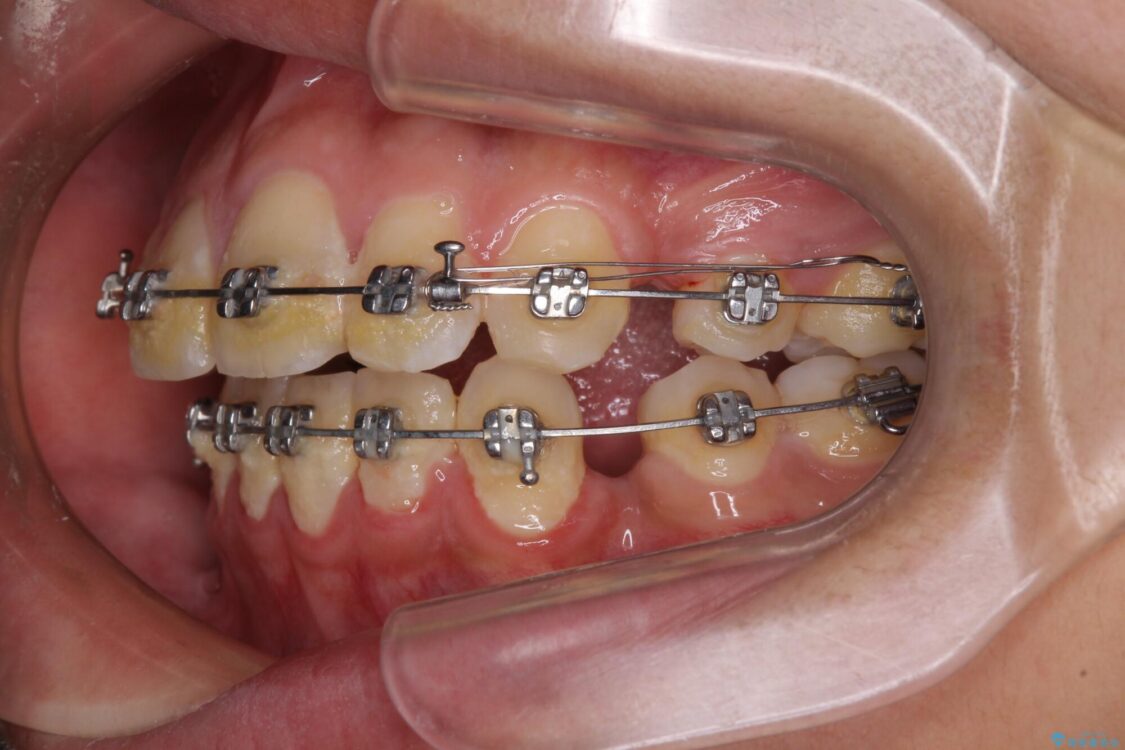

治療途中

• 膨らんだ口元 ワイヤー装置での抜歯矯正 治療途中画像